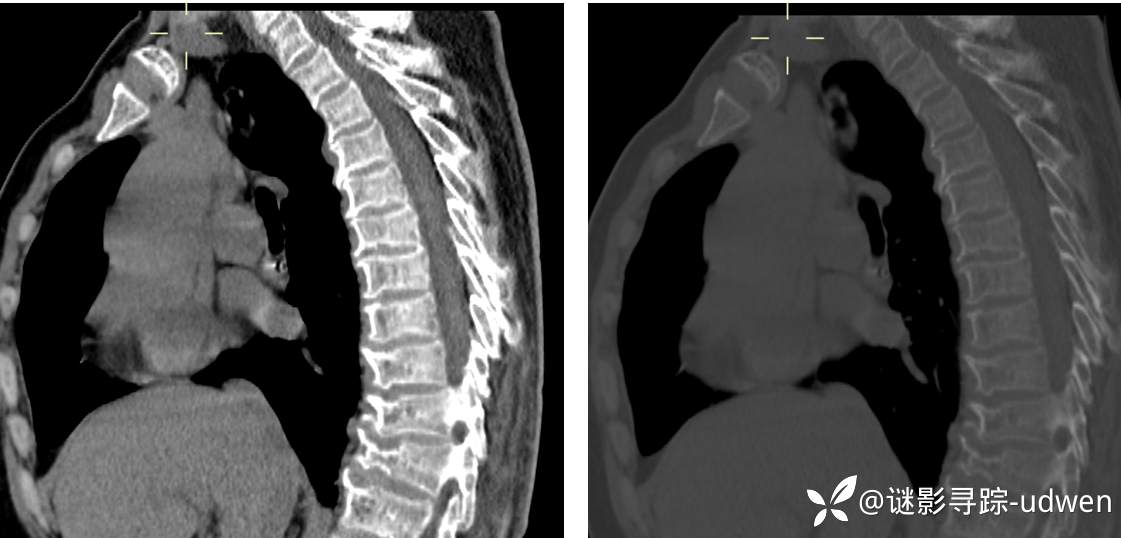

超级典型骨肌病例1例,X线已有人秒,补充MRI,胸部CT矢状位(答案公布)

患者性别:女

患者年龄:59岁

主诉:左小腿疼痛伴活动受限半年余

简要病史:患者本人及家属诉半年余前无明显诱因出现左小腿疼痛,疼痛逐渐加重,伴活动受限,无静息痛,无发热,无头痛、头晕,无咳嗽、咳痰,无胸闷、心悸、呼吸困难,无恶心、呕吐等不适